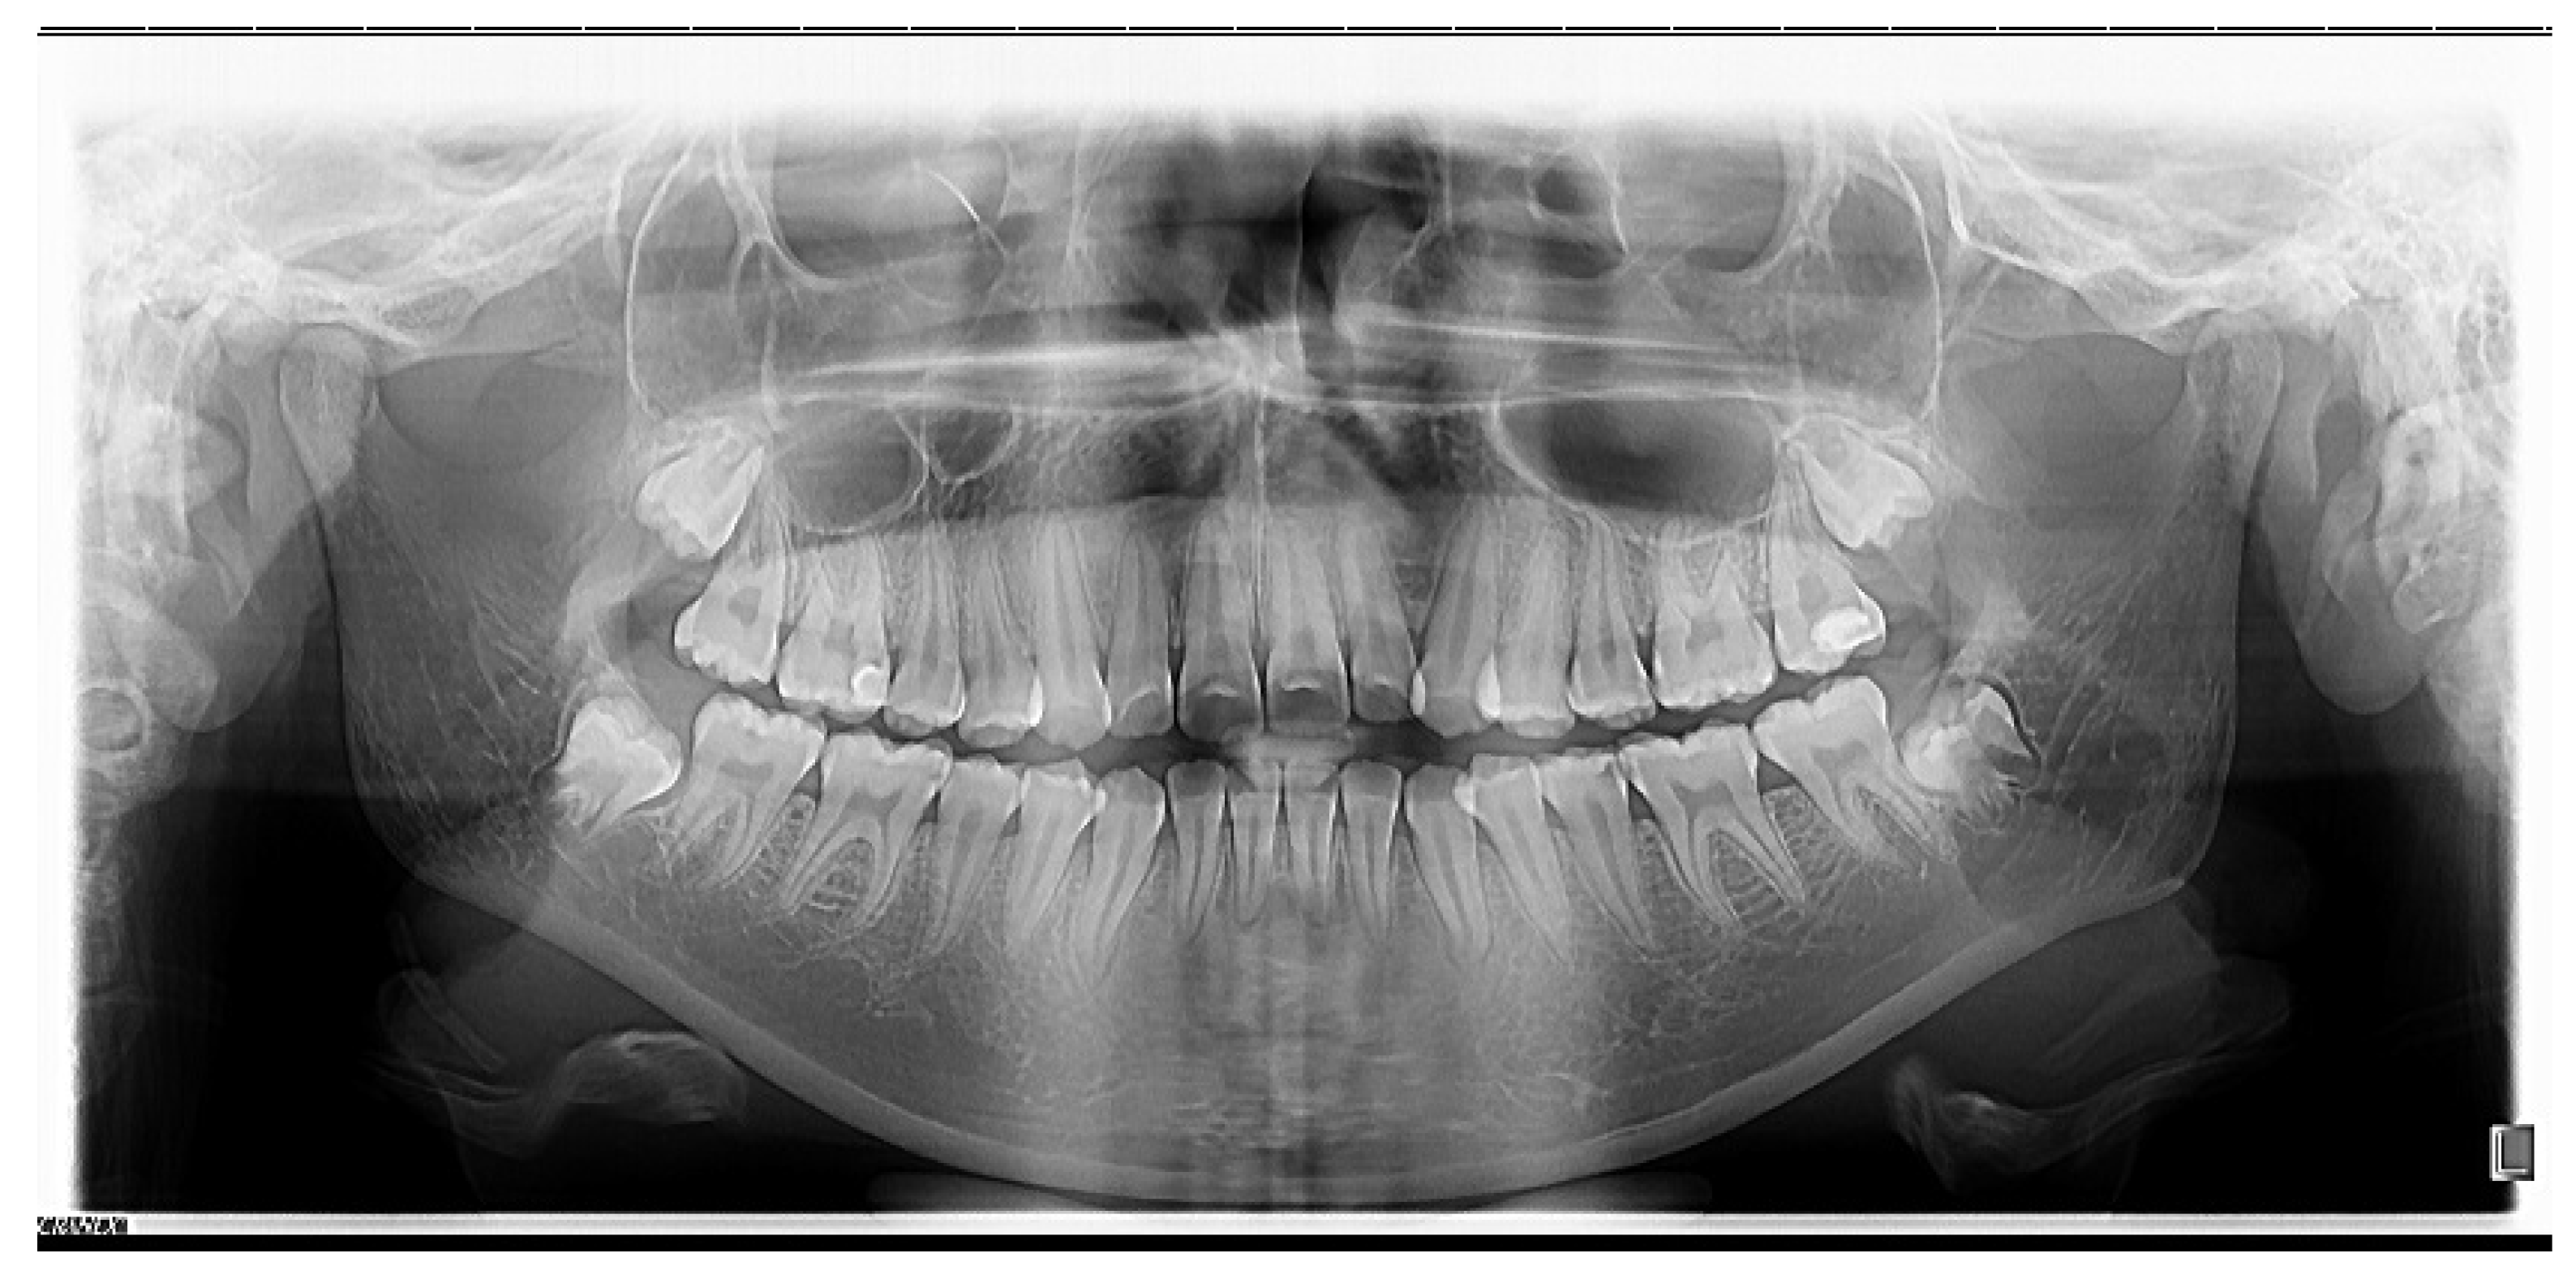

- Skeletal open bite in a 15.7-year-old patient with hyperleptoprosop morphological facial type (N-Gn/Zy-Zy = 111.66), high degree of hyperdivergence (FMA = 39.22°), bimaxillary dento-alveolar protrusion (IF = 120.85°, IMPA = 98.03°), 7 mm skeletal open-bite, and 3 mm vertical inocclusion of the anterior teeth;

- Skeletal class II relationships (SNA = 78.32°, SNB = 73.98°), bilateral half cusp class II molar and canine relationships;

- Labial incompetence, short upper lip, highly increased interlabial gap;

- Facial asymmetry;

- Excessive gingival exposure of 7 mm in smile;

- Bimaxillary anterior crowding.